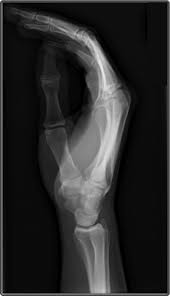

what projection is performed o image the thumb

AP AXIAL projection